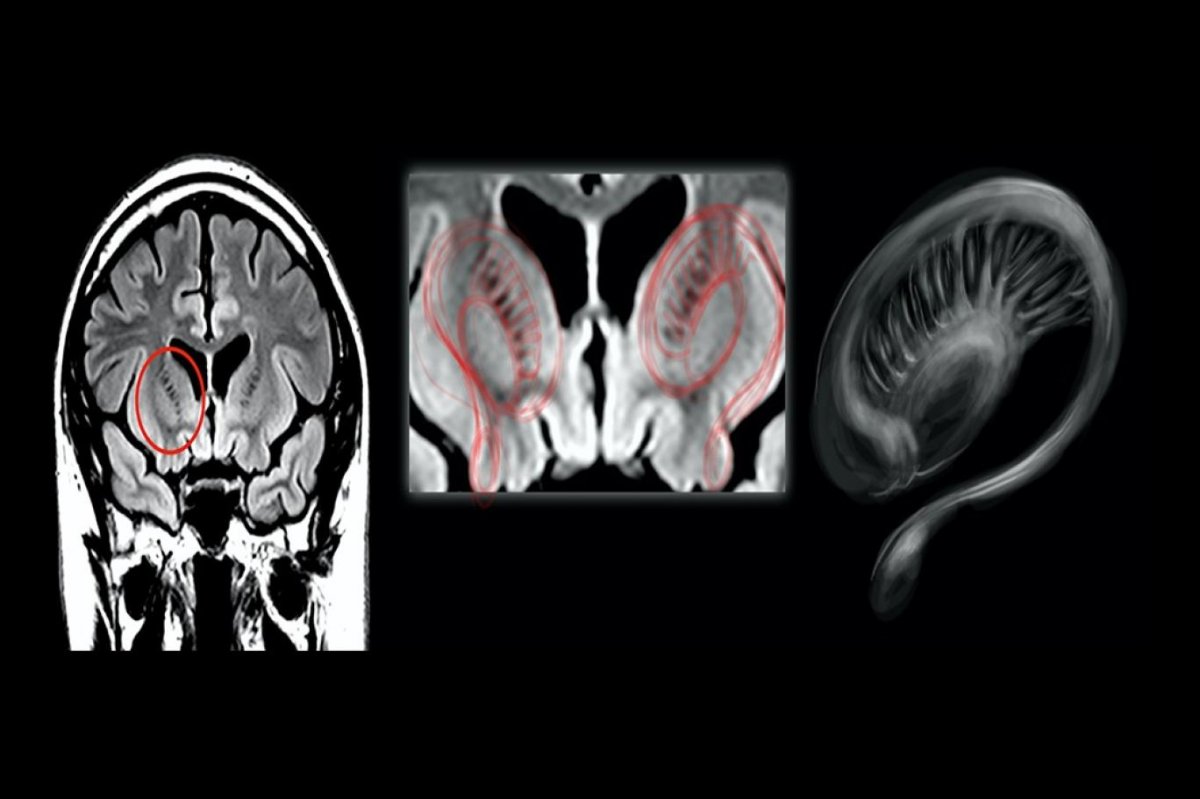

Muhabir Thobey Champion'ın isteği üzerine bu kişilerin MR görüntülerini tarif eden profesör, "Multipl skleroz hastası birinin MR'ına baktıysanız, beyaz cevher hastalığı denen bir şey görürsünüz. Yara izi vardır." ifadelerini kullandı:

"MR boyunca dağılmış büyük beyaz bir leke veya birden fazla beyaz leke görürsünüz. Bu aslında bağışıklık sisteminin beyne saldırdığı ölü dokudur. Pilotların beyin görüntülerine en yakın durum buydu. Bir şeylerin yanlış olduğunu hızla görebilirsiniz."